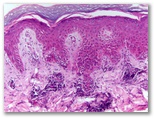

¿Granuloma anular?

Diagnostico